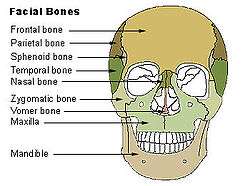

Nasal bone visible at center, in dark green. | |

The nasal bones are two small oblong bones, varying in size and form in different individuals; they are placed side by side at the middle and upper part of the face, and form, by their junction, "the bridge" of the nose.

The nasal articulates with four bones: two of the cranium, the frontal and ethmoid, and two of the face, the opposite nasal and the maxilla.

Side view of the skull. The skull from the front.

The skull from the front. Horizontal section of nasal and orbital cavities.